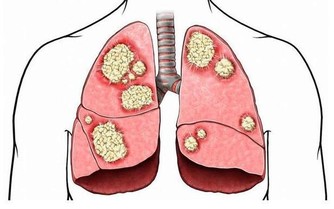

四、【鼻皺紋】:代表的器官是心臟

皺紋的暗示:鼻皺紋是遺傳來的皺紋,隨著年齡的增長,到年老時就會變得更為明顯。鼻皺紋代表的器官是心臟。每條皺紋分岔產生的細小分支皺紋對面部診斷醫師來說,都具有相應的意義。

如果鼻樑上出現許多十字形皺紋,不排除脊柱或腎臟有嚴重病變的可能性,有這種皺紋的人脊柱通常會變形。

應對的方法:為了增強心臟功能,可每天飲用少量紅葡萄酒,這被譽為最佳的心臟滋補飲料。同時使用富含純維生素C的護膚用品可以阻止皮膚下垂的功效。